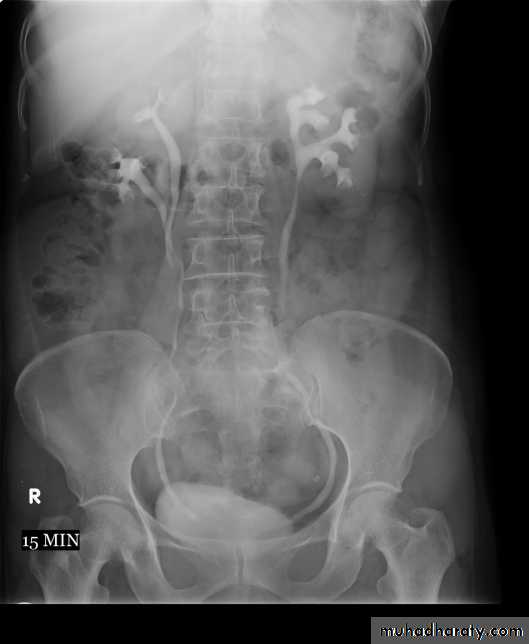

4. Full length film after release of compression .

Urinary system

5. A full bladder film (with the urinary bladder fully distended with contrast)